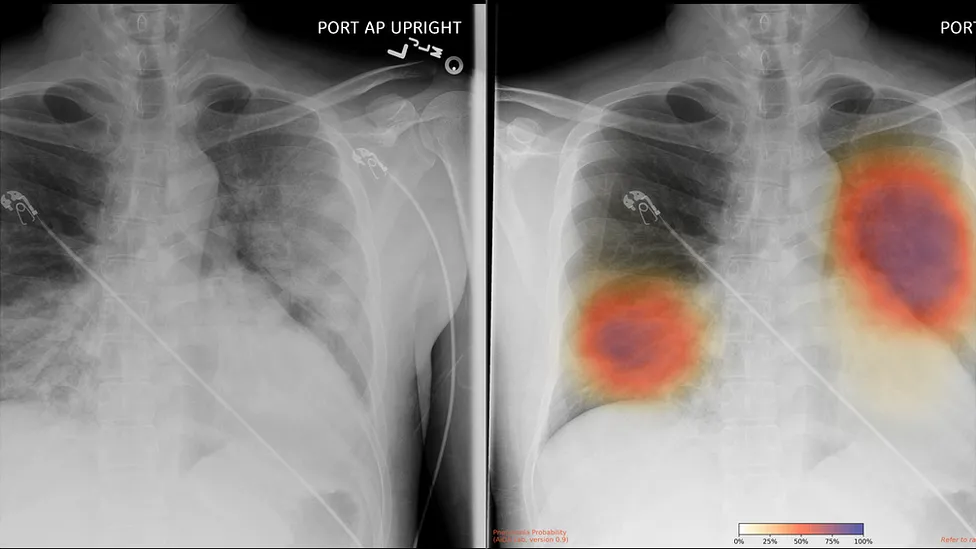

It has been running automatically on every chest X-ray the hospital has carried out for about a week, says Rizwan Malik, a radiology consultant at the hospital. This means more than 100 patients will have had X-rays analysed by the system to date, he estimates. In this case, the algorithm is designed to look for possible signs of Covid-19, such as patterns of opacity in the lungs.

”It basically gives clinicians another tool to help them make decisions - for example, which patients they’ll admit, which they’ll send home,” says Dr Malik, who notes that patient data is processed entirely within the hospital’s own network. The software itself was developed by Mumbai-based Qure.ai.